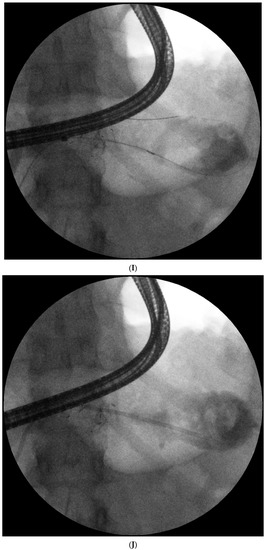

Figure 1. (A–L) Endoscopic treatment of walled-off pancreatic necrosis. In the second week of acute necrotizing pancreatitis, the acute necrotic collection (A) is visible in the abdominal contrast-enhanced computed tomography (CECT), which evolved in the sixth week of the illness duration into the symptomatic walled-off pancreatic necrosis (B). Patient qualified for endoscopic treatment (C–F) transmural drainage using the self-expanding metal stent (C,D) and endoscopic necrosectomy (E,F) was performed. In the second week of endotherapy, the endoscopic retrograde pancreatography (G–J) was performed. During pancreatography, the complete pancreatic duct disruption was stated (G–I) and transpapillary drainage was carried out (J). After achieving the treatment’s success and the complete regression of the necrotic collection, the transpapillary stent was observed in the bottom of the collection via the endoscopic view from the stomach’s side through the transmural stent (K). Control CECT confirmed the total regression of the collection (L).